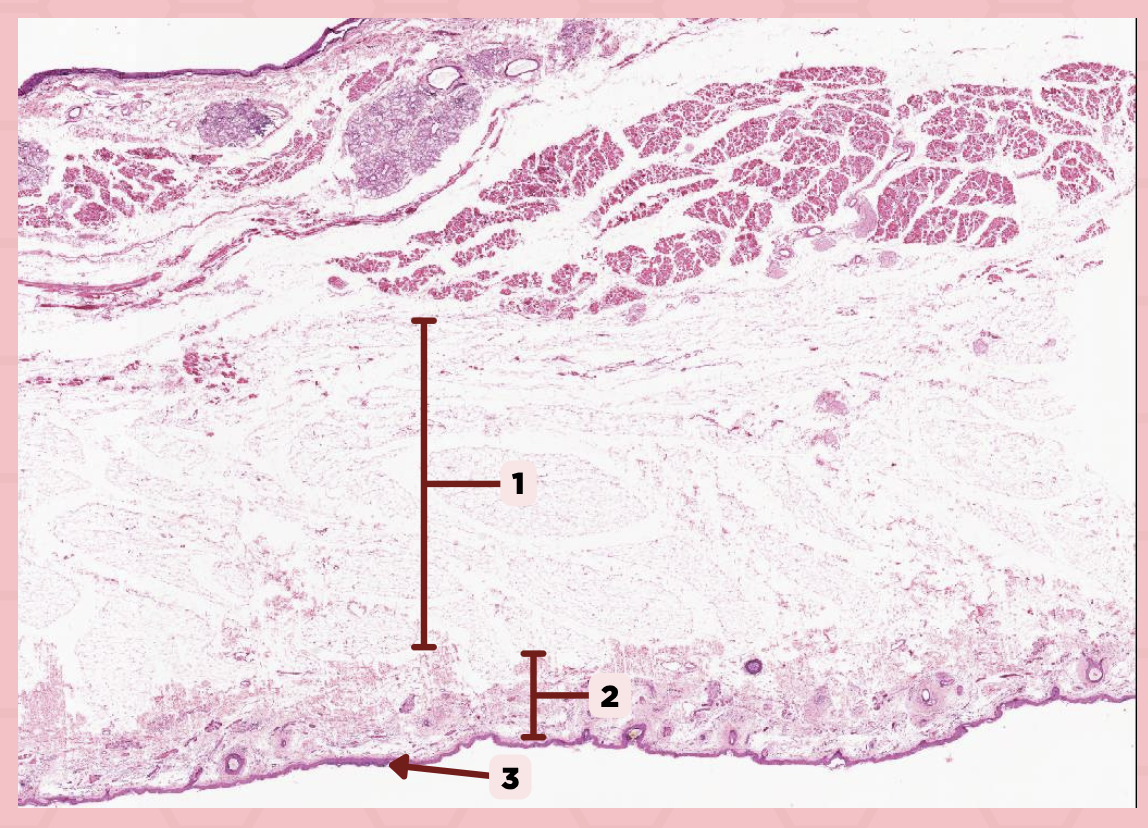

Lip

What specimen is being showed in this picture?

Keratinized Stratified Squamous Epithelium (Epidermis)

Identify the structure labeled as 1.

d. Mucosa/Mucous Membrane

Identify the structure labelled in the given image?

a. Epidermis

b. Dermis

c. Hypodermis

d. Mucosa/Mucous Membrane

b. Nonkeratinized stratified squamous epithelium

Identify the structure’s lining epithelium given in the image?

a. Keratinized stratified squamous epithelium

b. Nonkeratinized stratified squamous epithelium

Lip

What specimen is being showed in the picture?

Non-Keratinized Stratified Squamous Epithelium (Mucosa/Mucous Membrane)

Identify the structure labeled as 1.

a. Abrupt Transition from keratinized to nonkeratinized epithelium

Identify the structure’s lining epithelium given in the image?

a. Abrupt Transition from keratinized to nonkeratinized epithelium

b. Abrupt Transition from nonkeratinized to keratinized epithelium

c. AOTA

d. NOTA

Lip

What specimen is being showed in the picture?

Mucocutaneous Junction

Identify the structure labeled as 1.

Lip

What specimen is being showed in the picture?

Epidermis

Identify the structure labeled as 1.

Dermis

Identify the structure labeled as 2.

Arrector Pilli Muscle

Identify the structure labeled as 3.